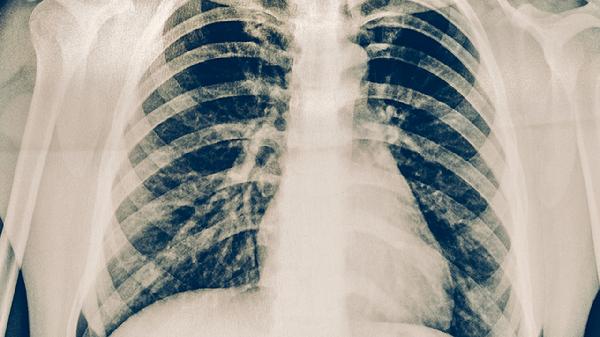

胸部X線檢查可以顯示肺部病變的位置、范圍和性質(zhì),是肺結(jié)核診斷的重要輔助手段。典型肺結(jié)核在X線片上表現(xiàn)為上肺野浸潤(rùn)性病變、空洞形成或纖維鈣化灶。但胸部X線檢查不能確診肺結(jié)核,需結(jié)合其他檢查結(jié)果進(jìn)行判斷。該方法適用于有呼吸道癥狀的可疑肺結(jié)核患者。